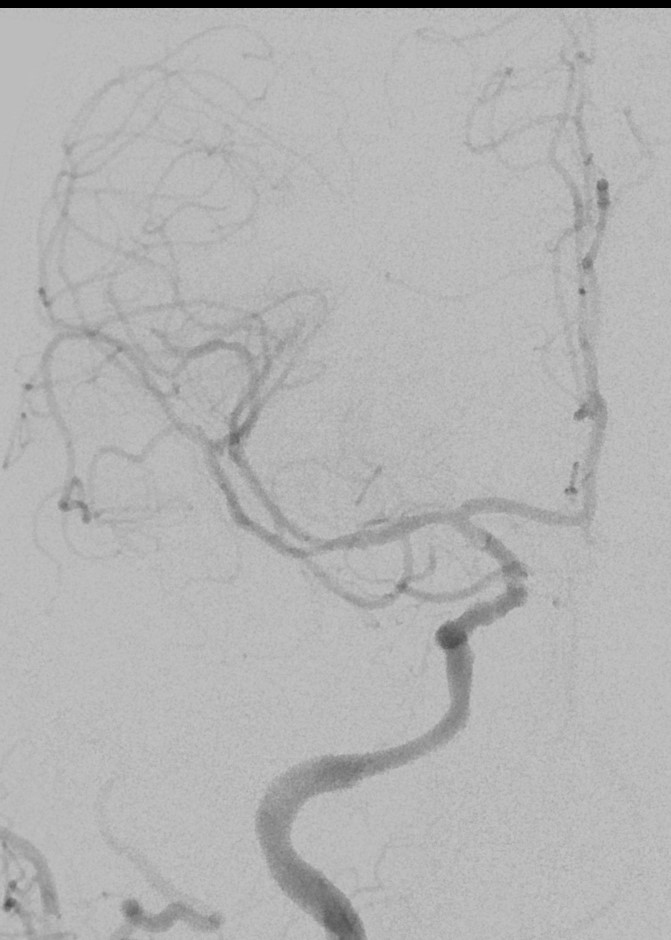

13:00 Больной подан в рентгеноперационную, выполнена церебральная ангиография: Ангиографические признаки атеросклеротического процесса брахиоцефальных артерий, тромботической окклюзии правой ВСА(Рис1), окклюзия левых ВСА(Рис3) и ПА(Рис2).

Рис4 заполнение системы левой ВСА через левую заднюю соединительную артерию.

рис. 3 рис. 4